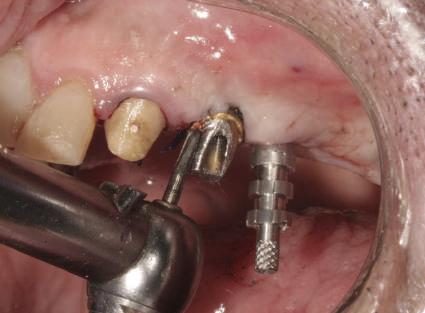

Repreparea intraorală a bonturilor cu amprente extraorale

Acest caz prezenta probleme de recesie similare cu cele menţionate anterior. Deşi bonturile au fost re-preparate intraoral pentru a urma noile margini tisulare, s-a decis amprentarea în afara cavităţii orale pentru a evita manipularea ţesutului pacientului cu biotip subţire. Fiecare bont individualizat s-a îndepărtat şi s-au inserat imediat bonturi de vindecare pentru a evita colapsul ţesuturilor.

Atitudine: Fiecare bont individualizat s-a aplicat pe câte un analog de implant. Fig. 6 prezintă bontul nou preparat pe analogul său cu inel de cupru de dimensiuni mari pentru a susţine

materialul de amprentare (alternativ, s-ar fi putut utiliza o lingură de amprentare universală pe cadran pentru a asigura suport pentru materialul de amprentare). Fig. 7 prezintă bontul individualizat cu ceară aplicată pentru a preveni pătrunderea materialului de amprentare în camera de acces a şurubului, iar fig. 8 ilustrează tehnica de amprentare care evită necesitatea plasării unui şnur de retracţie în şanţ în jurul implantului. Această tehnică este, de asemenea, utilă pentru adăugarea la marginile restaurării provizorii.

Cazul (2): Repreparea intraorală a bonturilor cu amprente extraorale

Figurile

6. Bontul nou preparat pe analog.

7. Bont individualizat cu vată şi ceară.

8. Tehnica de amprentare.